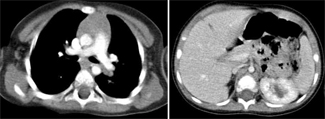

Recent researches on eating disorders state that the incidence of these disorders in men is fewer than in women, but serious doubts remain about the connection between the disorder and the gender of patients. Cases of anorexia nervosa in men have been studied, but...